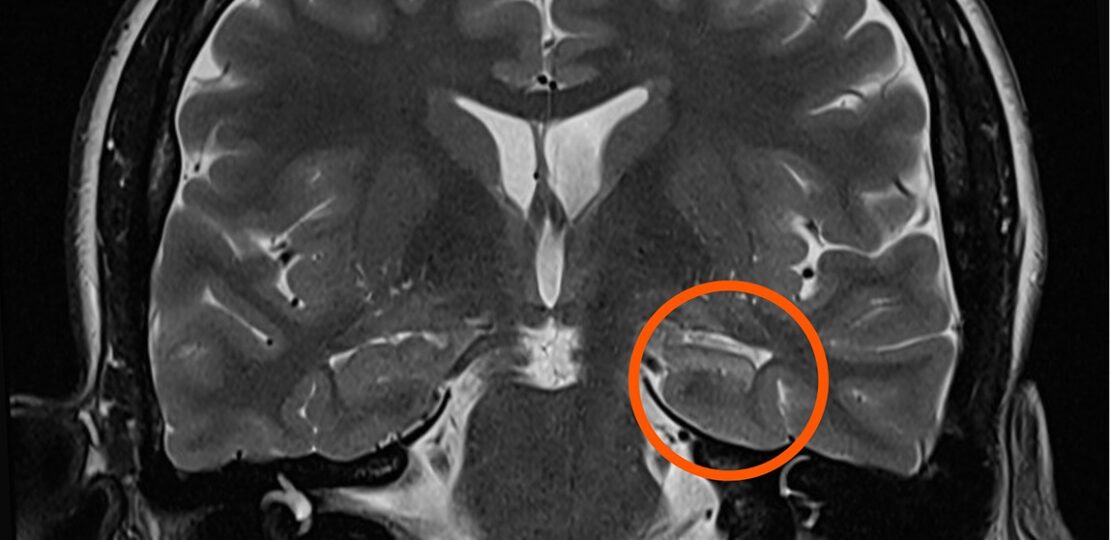

lobo temporal

• Ressecção focal: remoção da pequena área do cérebro que causa as crises (ex: lobectomia temporal)

• Ressonância magnética de alta resolução

A cirurgia não “cura” a epilepsia em todos os casos, mas pode eliminar as crises em até 60–80% dos pacientes, especialmente nos casos de epilepsia do lobo temporal.